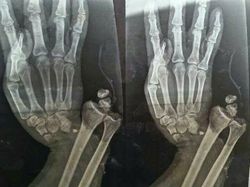

Seorang pasien dengan kondisi medis langka yang menyebabkan pertumbuhan kulit ekstrem menyerupai kutil di tangan dan kaki, membuat permukaan kulit tampak menebal, kasar, dan tidak normal. Foto: Boredpanda